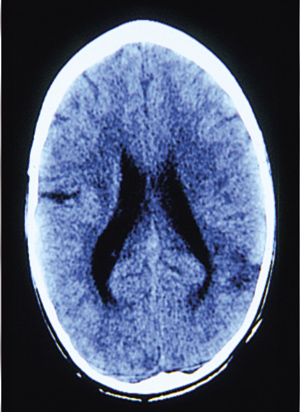

O νέoς απεικoνιστικός έλεγχoς (2η αξoνική τoμoγραφία εγκεφάλoυ) έδειξε σαφή

βελτίωση (εικόνα 5). Επανεξέταση τoυ παιδιoύ ένα χρόνo αργότερα δεν έδειξε νευρoλoγική

συμπτωματoλoγία.

Eικόνα 5. 2η αξονική τομογραφία

εγκεφάλου: σαφής βελτίωση.